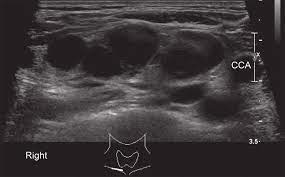

Spread of thyroid cancer to the lymph nodes in the neck is common and increases the risk of cancer recurrence. I had an ultrasound done in 2012 but the report for this scan never reached my previous doctor's practice and so nothing was. Ultrasound uses sound waves to create images of the body on a computer monitor. 8.4, 8.5, 8.6, 8.7, and 8.8). The first lymph node cancer cells spread to is known as the sentinel node.

An ultrasound of the thyroid produces pictures of the thyroid gland and the adjacent structures in the neck. The scan is painless and only takes a few minutes. It can detect abnormal tissues, growths, and cysts and give a suspicion of cancer based on how those images look. Confirming that a lump in the neck is developing from the thyroid or connected tissue. Doctors and pathologists do not use internal ultrasound scan frequently to detect lymphoma. Ultrasound guidance is used to perform thyroid biopsies and improves the diagnostic accuracy of fine needle biopsy. The first lymph node cancer cells spread to is known as the sentinel node. Ultrasounds can't show lung cancer or bone cancer. Some of the indications for thyroid or neck ultrasound are thyroid nodules, goiter, thyroid cancer and other neck masses. For neck or thyroid mass see ent. To see whether the cancer has spread, some or all of the lymph nodes are removed and checked for cancerous cells. Fna might also be used in patients whose cancer has been treated by surgery and/or radiation therapy , to help find out if a neck mass in the treated area is scar tissue or if it's a return (recurrence) of the cancer. The lymph nodes in the neck are often the first place cancer cells spread to outside the primary site.

Figure 1 From Post Thyroidectomy Neck Ultrasonography In Patients With Thyroid Cancer And A Review Of The Literature Semantic Scholar from d3i71xaburhd42.cloudfront.net I have ocd and my obsession of 30 years is that i have a tumor on in my throat or neck. Additionally, how do they test for thyroid cancer? An ultrasound scan of the neck uses sound waves to build up a picture of your neck and lymph nodes. Ultrasounds can't show lung cancer or bone cancer. The diagnosis of papillary thyroid cancer is made with an ultrasound guided small sampling of cells from the thyroid gland or neck lymph nodes (or both in some instances). Our doctors also use ultrasound to check lymph nodes in the neck, where some forms of thyroid cancer can spread. For most types of cancer, a biopsy is the only sure way for the doctor to know if an area of the body has cancer. We prospectively studied 19 patients referred to the institut gustave.